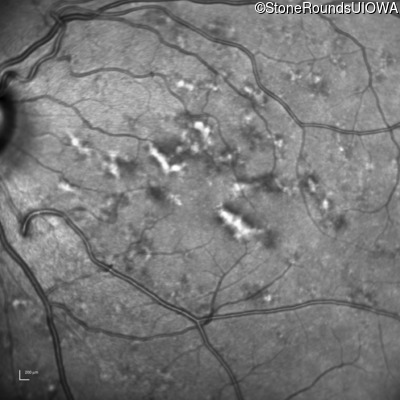

Blue Autofluorescence - Right - 20/15

Exemplar